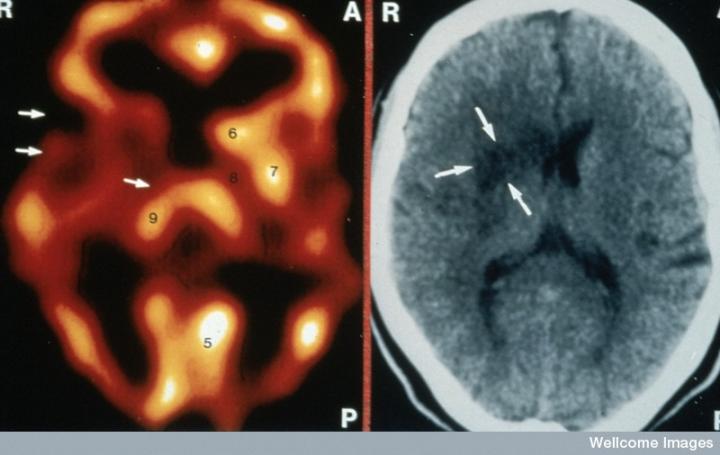

CT掃描的主圖顯示左側(cè)有一些中風(fēng)損傷,由 Wellcome Images提供。Wellcome Photo Library提供的慢性中風(fēng)的附加圖像 ,Wellcome Images,QL 從胚胎干細(xì)胞培養(yǎng)的神經(jīng)元。Ying & A. Smith, Wellcome Images 和 Yirui Sun, Wellcome Images 移植的小鼠神經(jīng)干細(xì)胞。